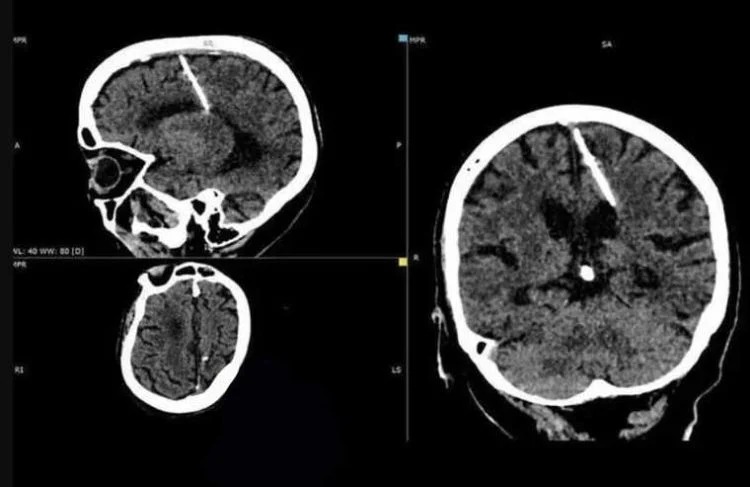

كشفت الآشعة المقطعية لعجوز بالغة من العمر 80 عامًا، من منطقة سخالين الروسية، أن لديها إبرة معدنية مقاس 3 سم مغروزة في الجانب الأيسر من دماغها.

ووفقًا لـ odditycentral، نشرت وزارة الصحة في سخالين مؤخرًا صورًا لنتائج الآشعة المقطعية للمرأة، مع تفسير صادم، حيث يعتقد الأطباء أن الإبرة تم إدخالها إلى دماغها من قبل والديها، بعد وقت قصير من ولادتها، وبقدر ما يبدو ذلك صادما، فإن مثل هذه الممارسات كانت شائعة في روسيا التي مزقتها الحرب.